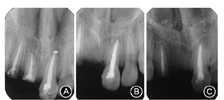

患者女性,19岁,2011年12月就诊于北京大学口腔医学院·口腔医院修复科,要求种植修复缺失的上前牙。7年前因上前牙外伤就诊于北京大学口腔医学院·口腔医院儿童口腔科,行12—21根管治疗(图1),6.5年前11残根因感染松动拔除(图2)。患者否认系统病和家族史。

根尖X线片示12、21根充恰填,根尖周未见明显异常(图4);锥形束CT示11牙槽嵴顶宽约3 mm,骨高度约15 mm,Ⅱ类骨;12唇侧骨板完整,厚约1 mm,根尖区可利用骨高度5 mm;头颅侧位X线片示骨性Ⅰ类错

;曲面体层X线片示75根管及髓腔内充填物,牙根吸收。